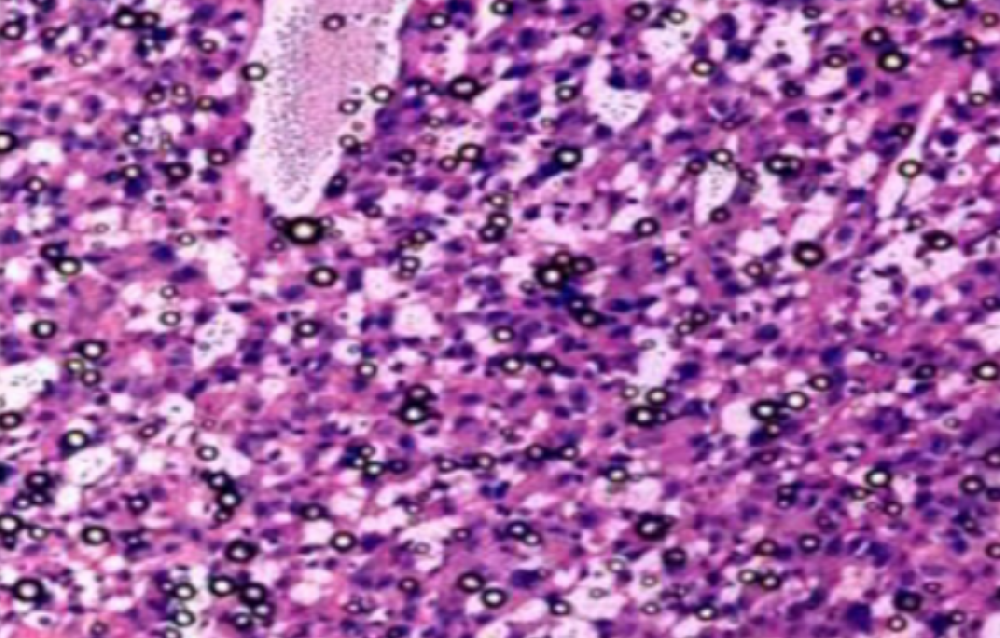

临沂组织病理学实验